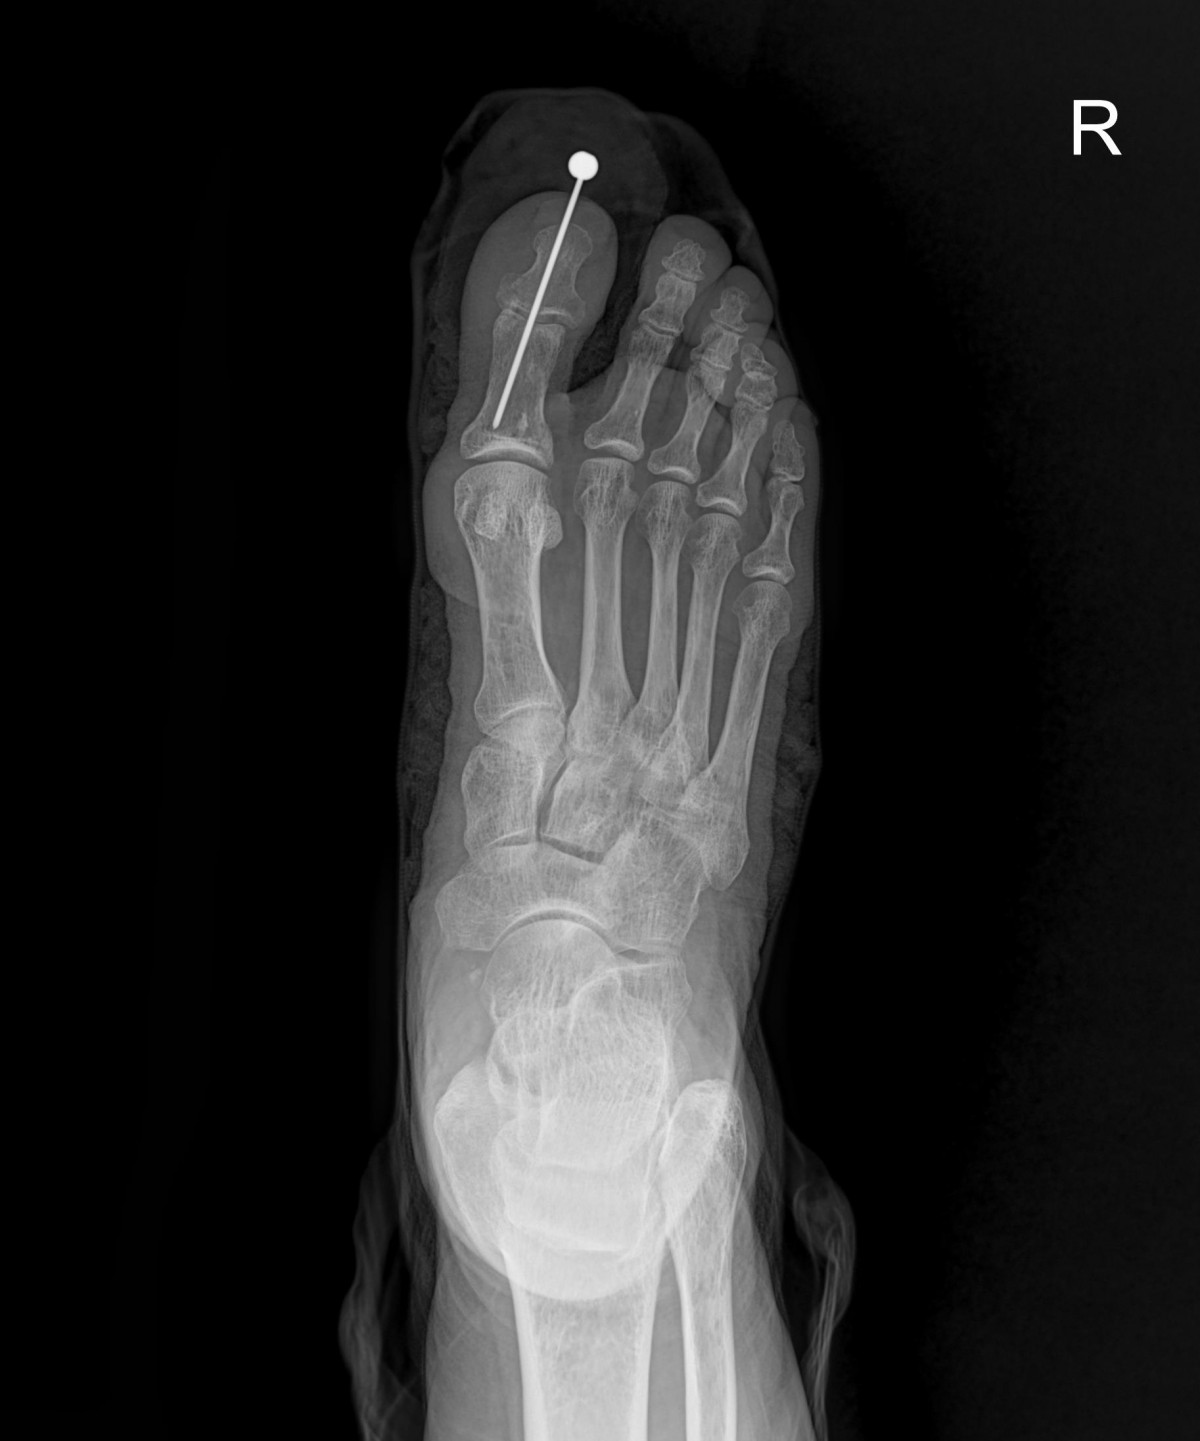

이재상원장님 발가락 골절 수술 이병O 환자

작성자 최고관리자 댓글 0건 조회 1,716회 작성일 24-10-16 16:31